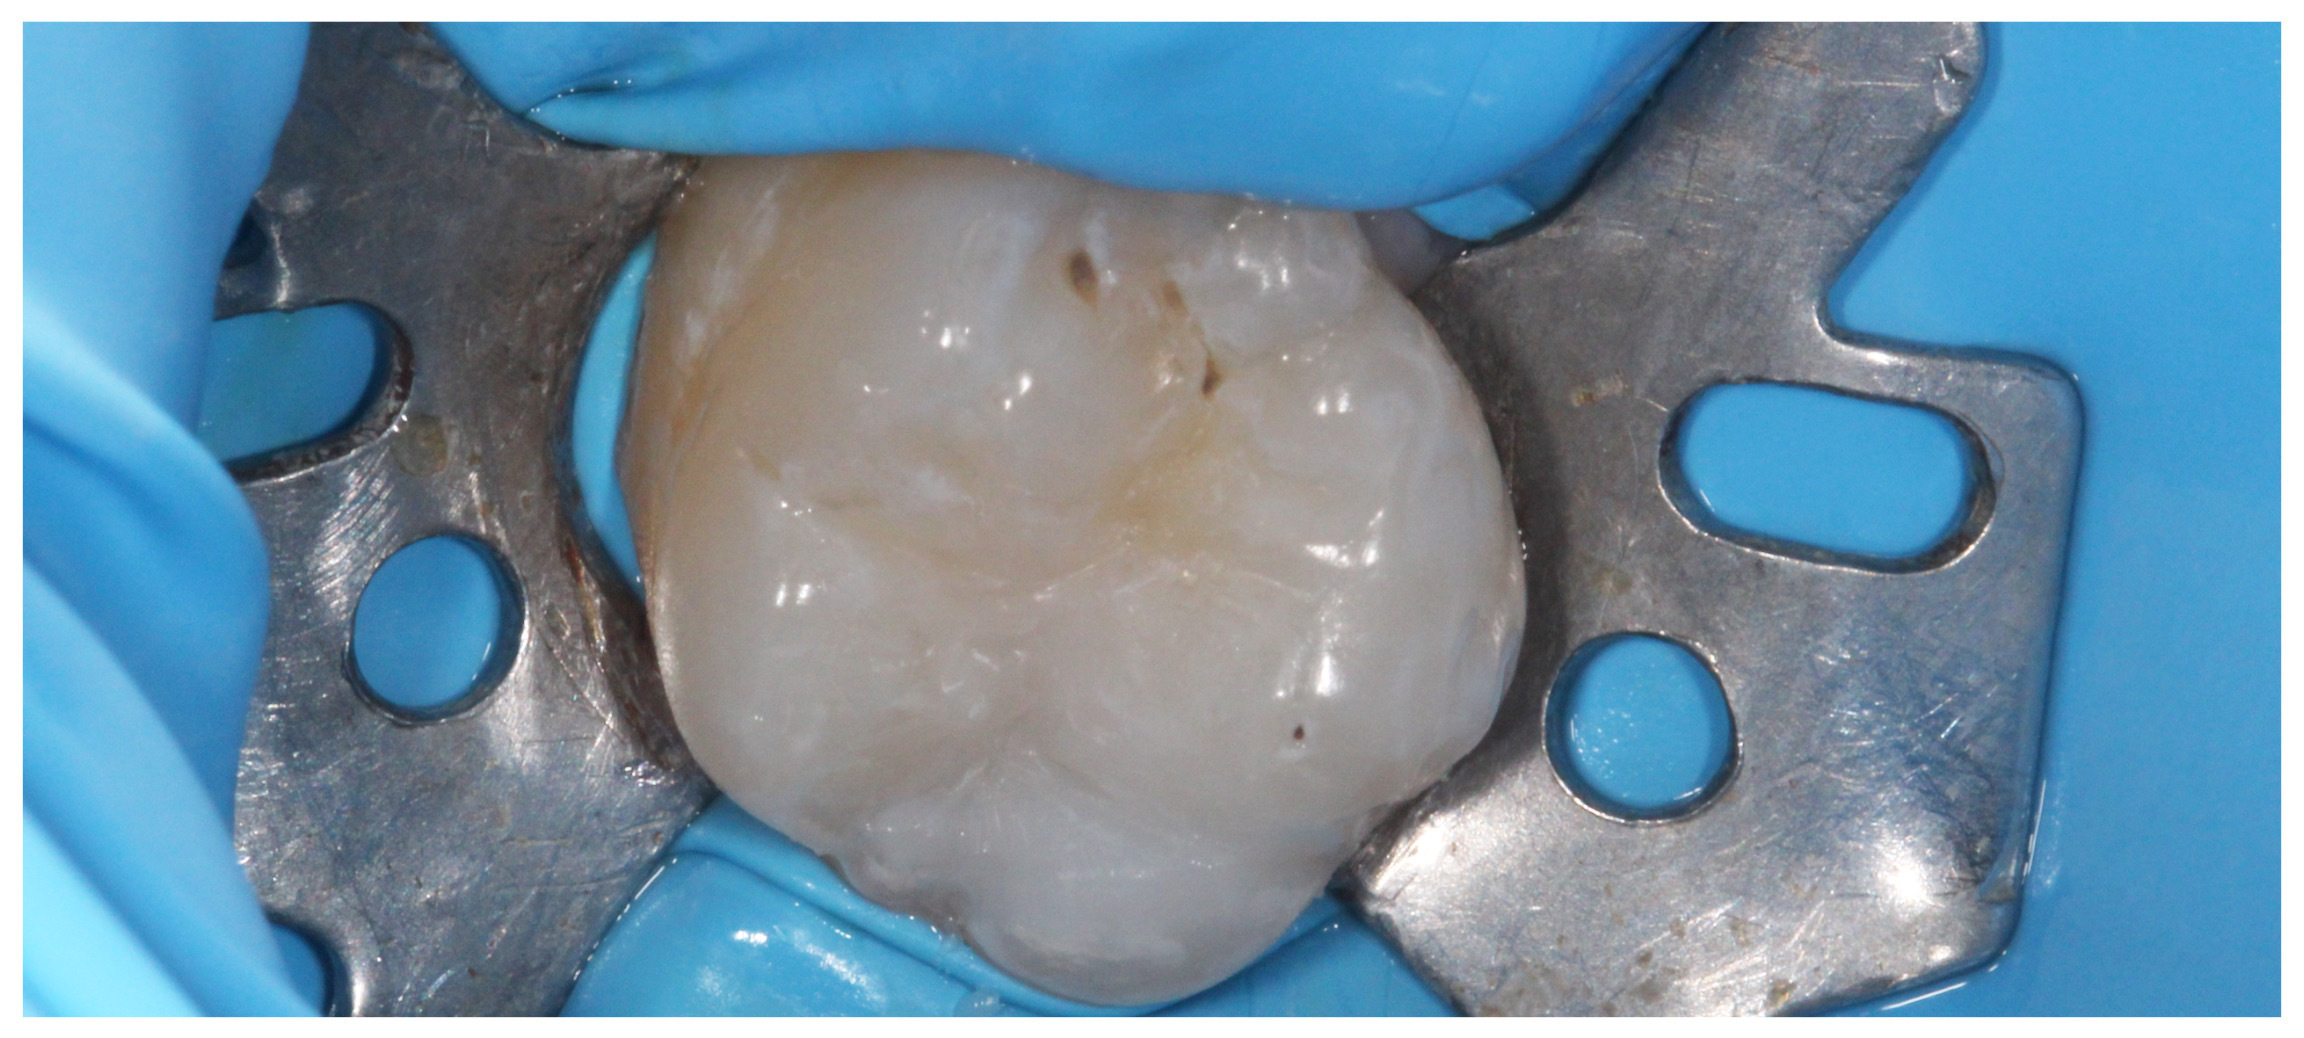

„White“ filling with caries on the first molar, new caries on the second molar

New photocomposite fillings